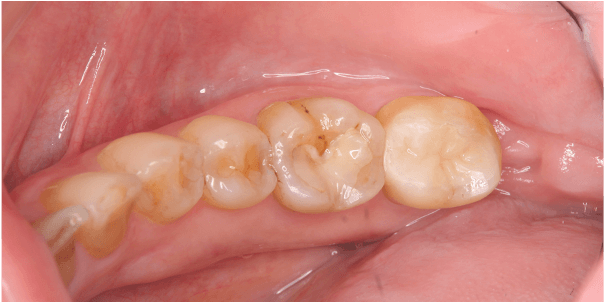

40歳女性のビフォーアフター

| 診断 | インレー脱離(被せものが取れた)、カリエス(虫歯) |

|---|---|

| 治療方針 | カリエスを除去し、形を整えた後にセラミックインレーを装着 |

| 治療費 ※ | 55000円(税込) |

| 治療期間 | 1カ月 |

| リスク | 割れるリスクあり |

※ 治療費は、治療当時の費用で、現在の費用と異なる可能性があります。現在の費用は治療費のページでご確認くださいませ。